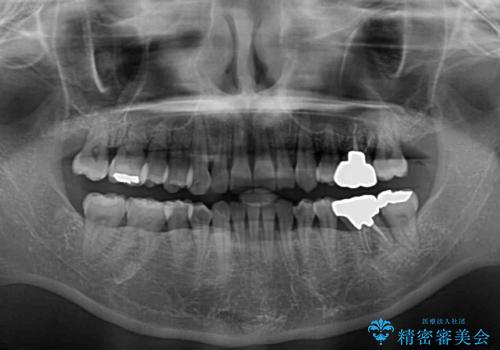

- 八重歯と正中のズレを気にして来院された患者様です。

上顎左側が八重歯になっており、上顎正中が左側にずれていました。

上顎左側の第一小臼歯を抜歯し、補助装置を用いて正中位置を改善しながら八重歯を解消していくこととしました。

下顎前歯が1本欠損していたため、上下正中の位置が合わせるという目標はなく、鼻筋に上顎正中を合わせていくように移動を行いました。